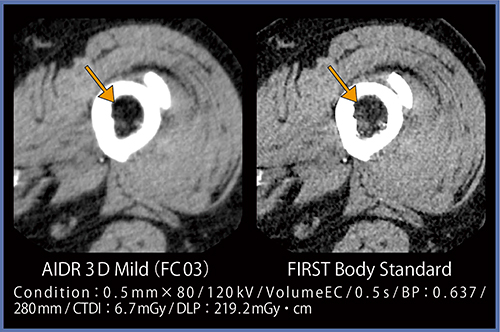

●症例8:交通外傷

本症例は上肢挙上困難であり,CTにて肘の付近に強いストリークアーチファクトが発生した。胸水が貯留しているものの,AIDR 3Dでは血性胸水かどうかの判断は困難であるが,FIRSTではアーチファクトがかなり低減し,胸水の濃度が評価しやすくなっている(図10)。

図10 症例8:交通外傷